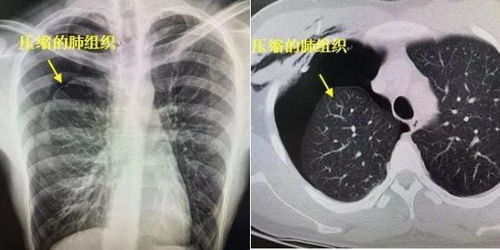

突然出現(xiàn)胸痛、呼吸困難應(yīng)立即到醫(yī)院做X線檢查,胸片上顯示無(wú)肺紋理的均勻透亮區(qū)的胸膜腔積氣帶,其內(nèi)側(cè)為弧形的線狀肺壓縮邊緣,可確診稱為氣胸。但有其他一些急癥也有類似表現(xiàn),如急性心肌梗塞、急性肺栓塞、肺大皰、急腹癥等,如果X線檢查未見(jiàn)氣胸征象,應(yīng)立即做進(jìn)一步檢查以明確病因,如心電圖等。